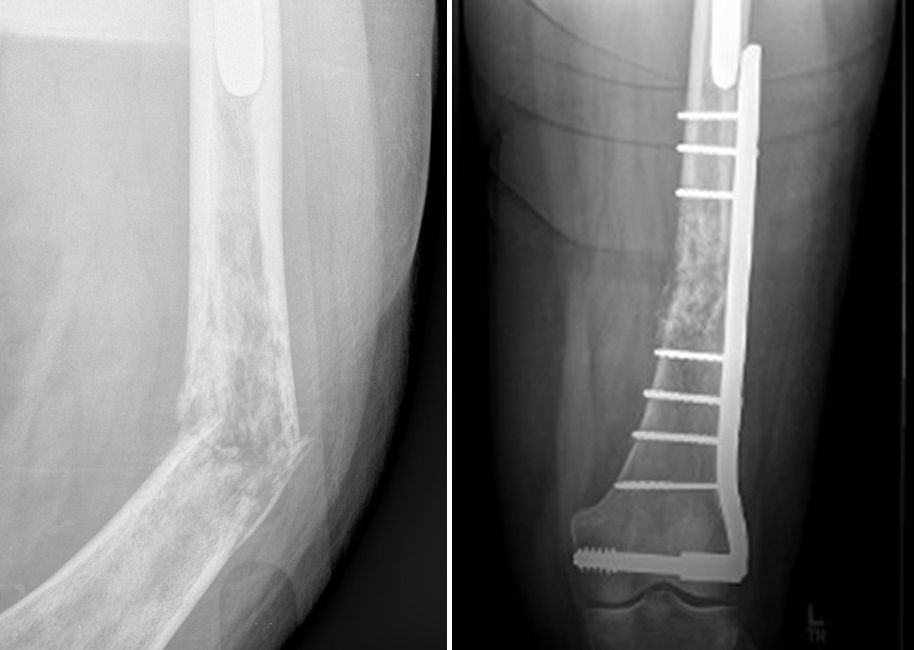

Internal fixation of pathologic fracture

(Left) In this X-ray, a tumor has weakened the femur (thighbone), causing it to fracture. (Right) Here, the fracture has been repaired with a plate and screws.

(Left) Reproduced from Biermann JS, ed: Orthopaedic Knowledge Update: Musculoskeletal Tumors 3. Rosemont, IL, American Academy of Orthopaedic Surgeons, 2014, p 205.